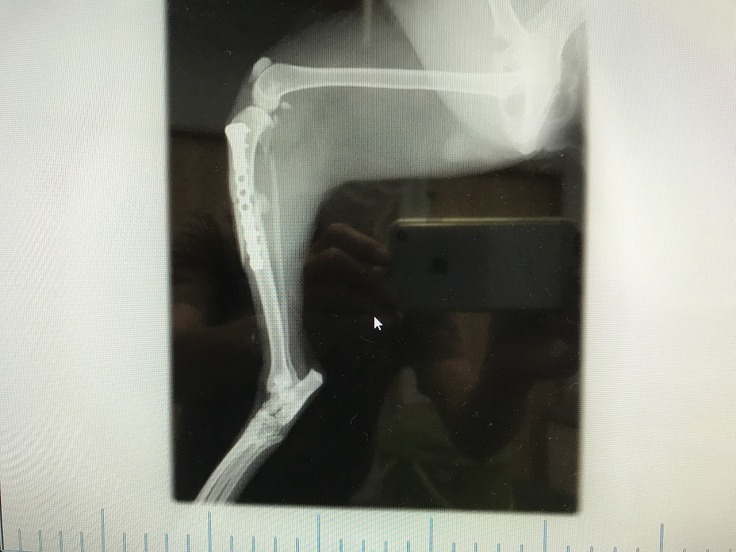

翌日、動物病院でレントゲンを撮影すると、右足の膝下を骨折していました。

8月20日に手術を受けました。

手術は、上手くいきましたが、骨がなかなか繋がらなくて、チビが動いてしまうために骨を固定しているプレートがズレて、再手術を受けました。

骨は何とか微妙につながりましたが、手術跡の皮膚が再生しませんでした。

骨がなかなか繋がらなくて2回の手術をうけましたが、真っ直ぐに上手くつながりませんでした。